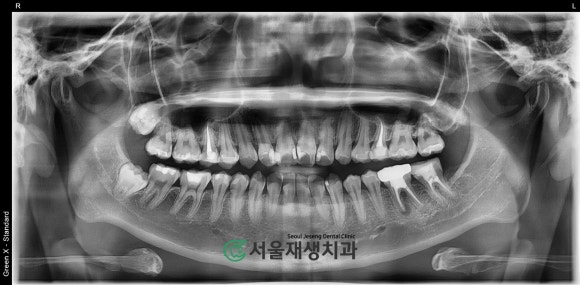

기본 영상 검사부터 해볼까요?

전반적인 구강상태 및

원인치아 파악에 필수적인

파노라마 엑스레이를 촬영해봅니다.

사진상으로 우측 하단의 어금니가

심상치 않습니다!

(실제로는 좌측 어금니입니다)

뿌리를 둘러싼 검은 그림자가 보이네요.

엑스레이 영상에서 검은색은

비어있는 공간을 의미합니다.

뼈로 가득차있어야 하는데

왜 비어있을까요?

확대하여 촬영해보겠습니다.